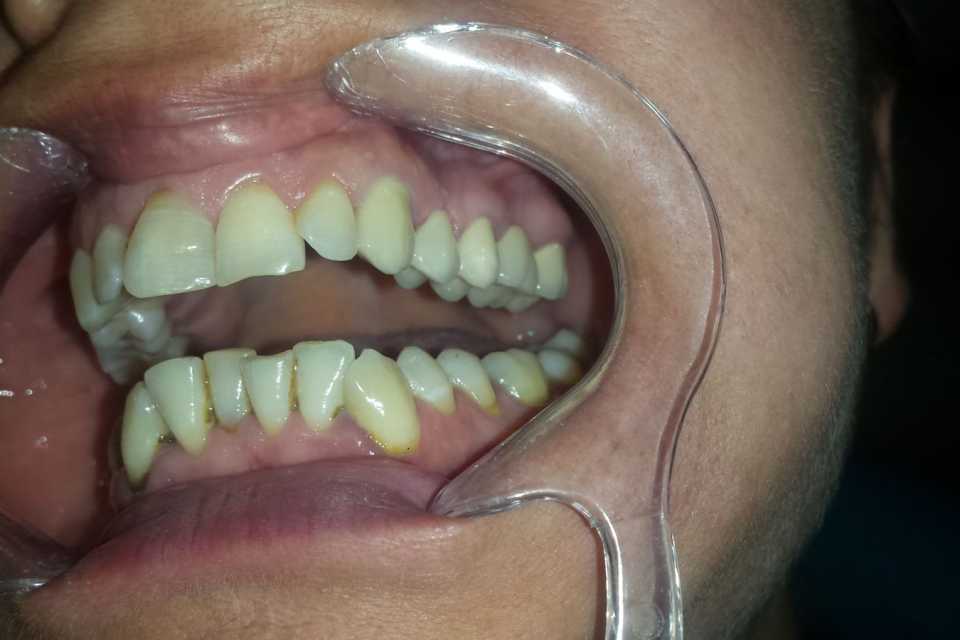

Pacienta s-a prezentat în cabinet din motive estetice și funcționale, acuzând sângerări gingivale și un miros neplacut. Am îndepărtat vechea lucrare, am refăcut tratamentele de canal, bonturile protetice și am slefuit bonturile cu prag.